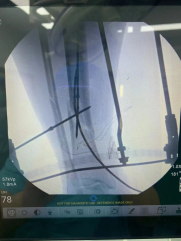

【胫腓骨骨折 】

(术者:CO接骨专家史医师)

【术中手术图】